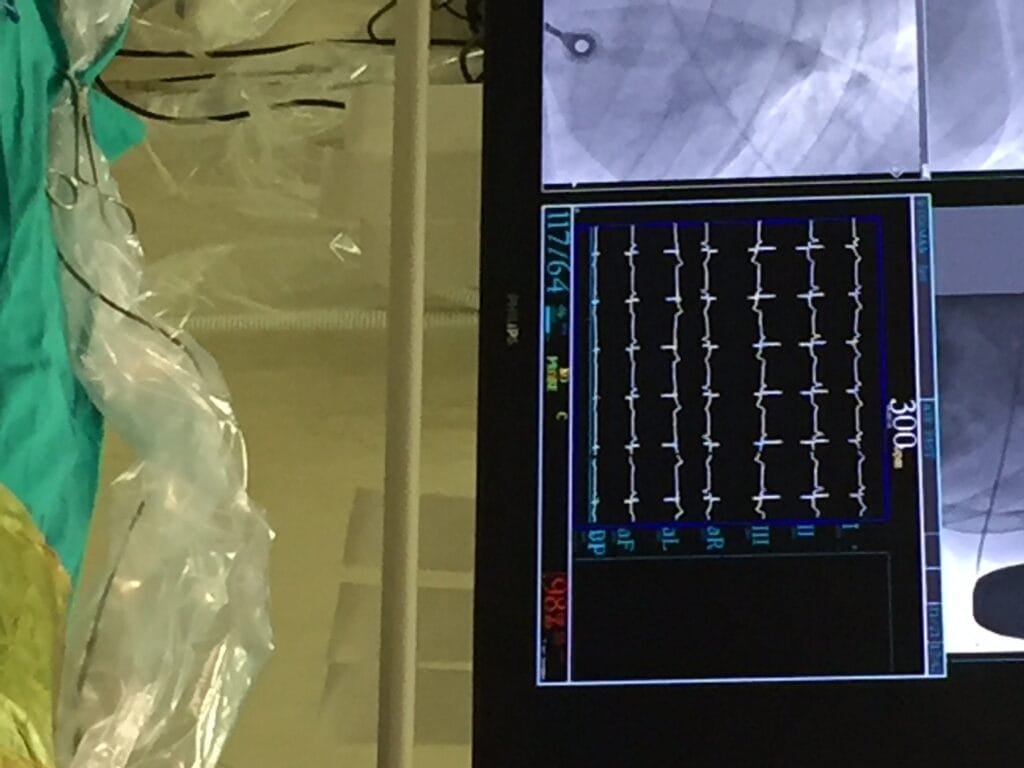

Step 7: Dr Gopal and team check that there is no air trapped in the tunnel. They also check that the lead is positioned as close as possible to the bone. This is of particular importance in a patient with a high body fat content, since fat around the lead will increase electrical resistance and may disrupt the electrical signals.

Step 8: With the device and lead in place, the doctor stimulates the heart to create ventricular tachycardia in the patient, to check if the device will recognise and diagnose a potentially fatal heart rhythm immediately and deliver an appropiate shock to the heart in order for the heart to regain normal (sinus) rhythm. The shock was administer at 13:21 and the device reacted 14 seconds later to shock the heart back into normal rhythm.